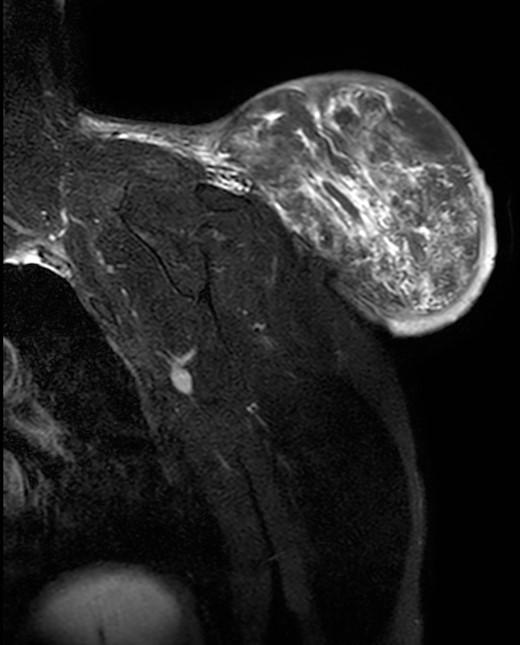

During the follow-up, a magnetic resonance (Figs 3 and 4) was performed describing a soft tissue lesion highly suggestive for liposarcoma as a first possibility diagnosis, with an addition image suggesting metastatic axillary lymph node. After the imaging results, biopsies were taken and analysed by the pathologist with a final diagnosis of PL.

Magnetic resonance imaging T1: polylobulated lesion with multiple septa separating different areas of fat tissue.